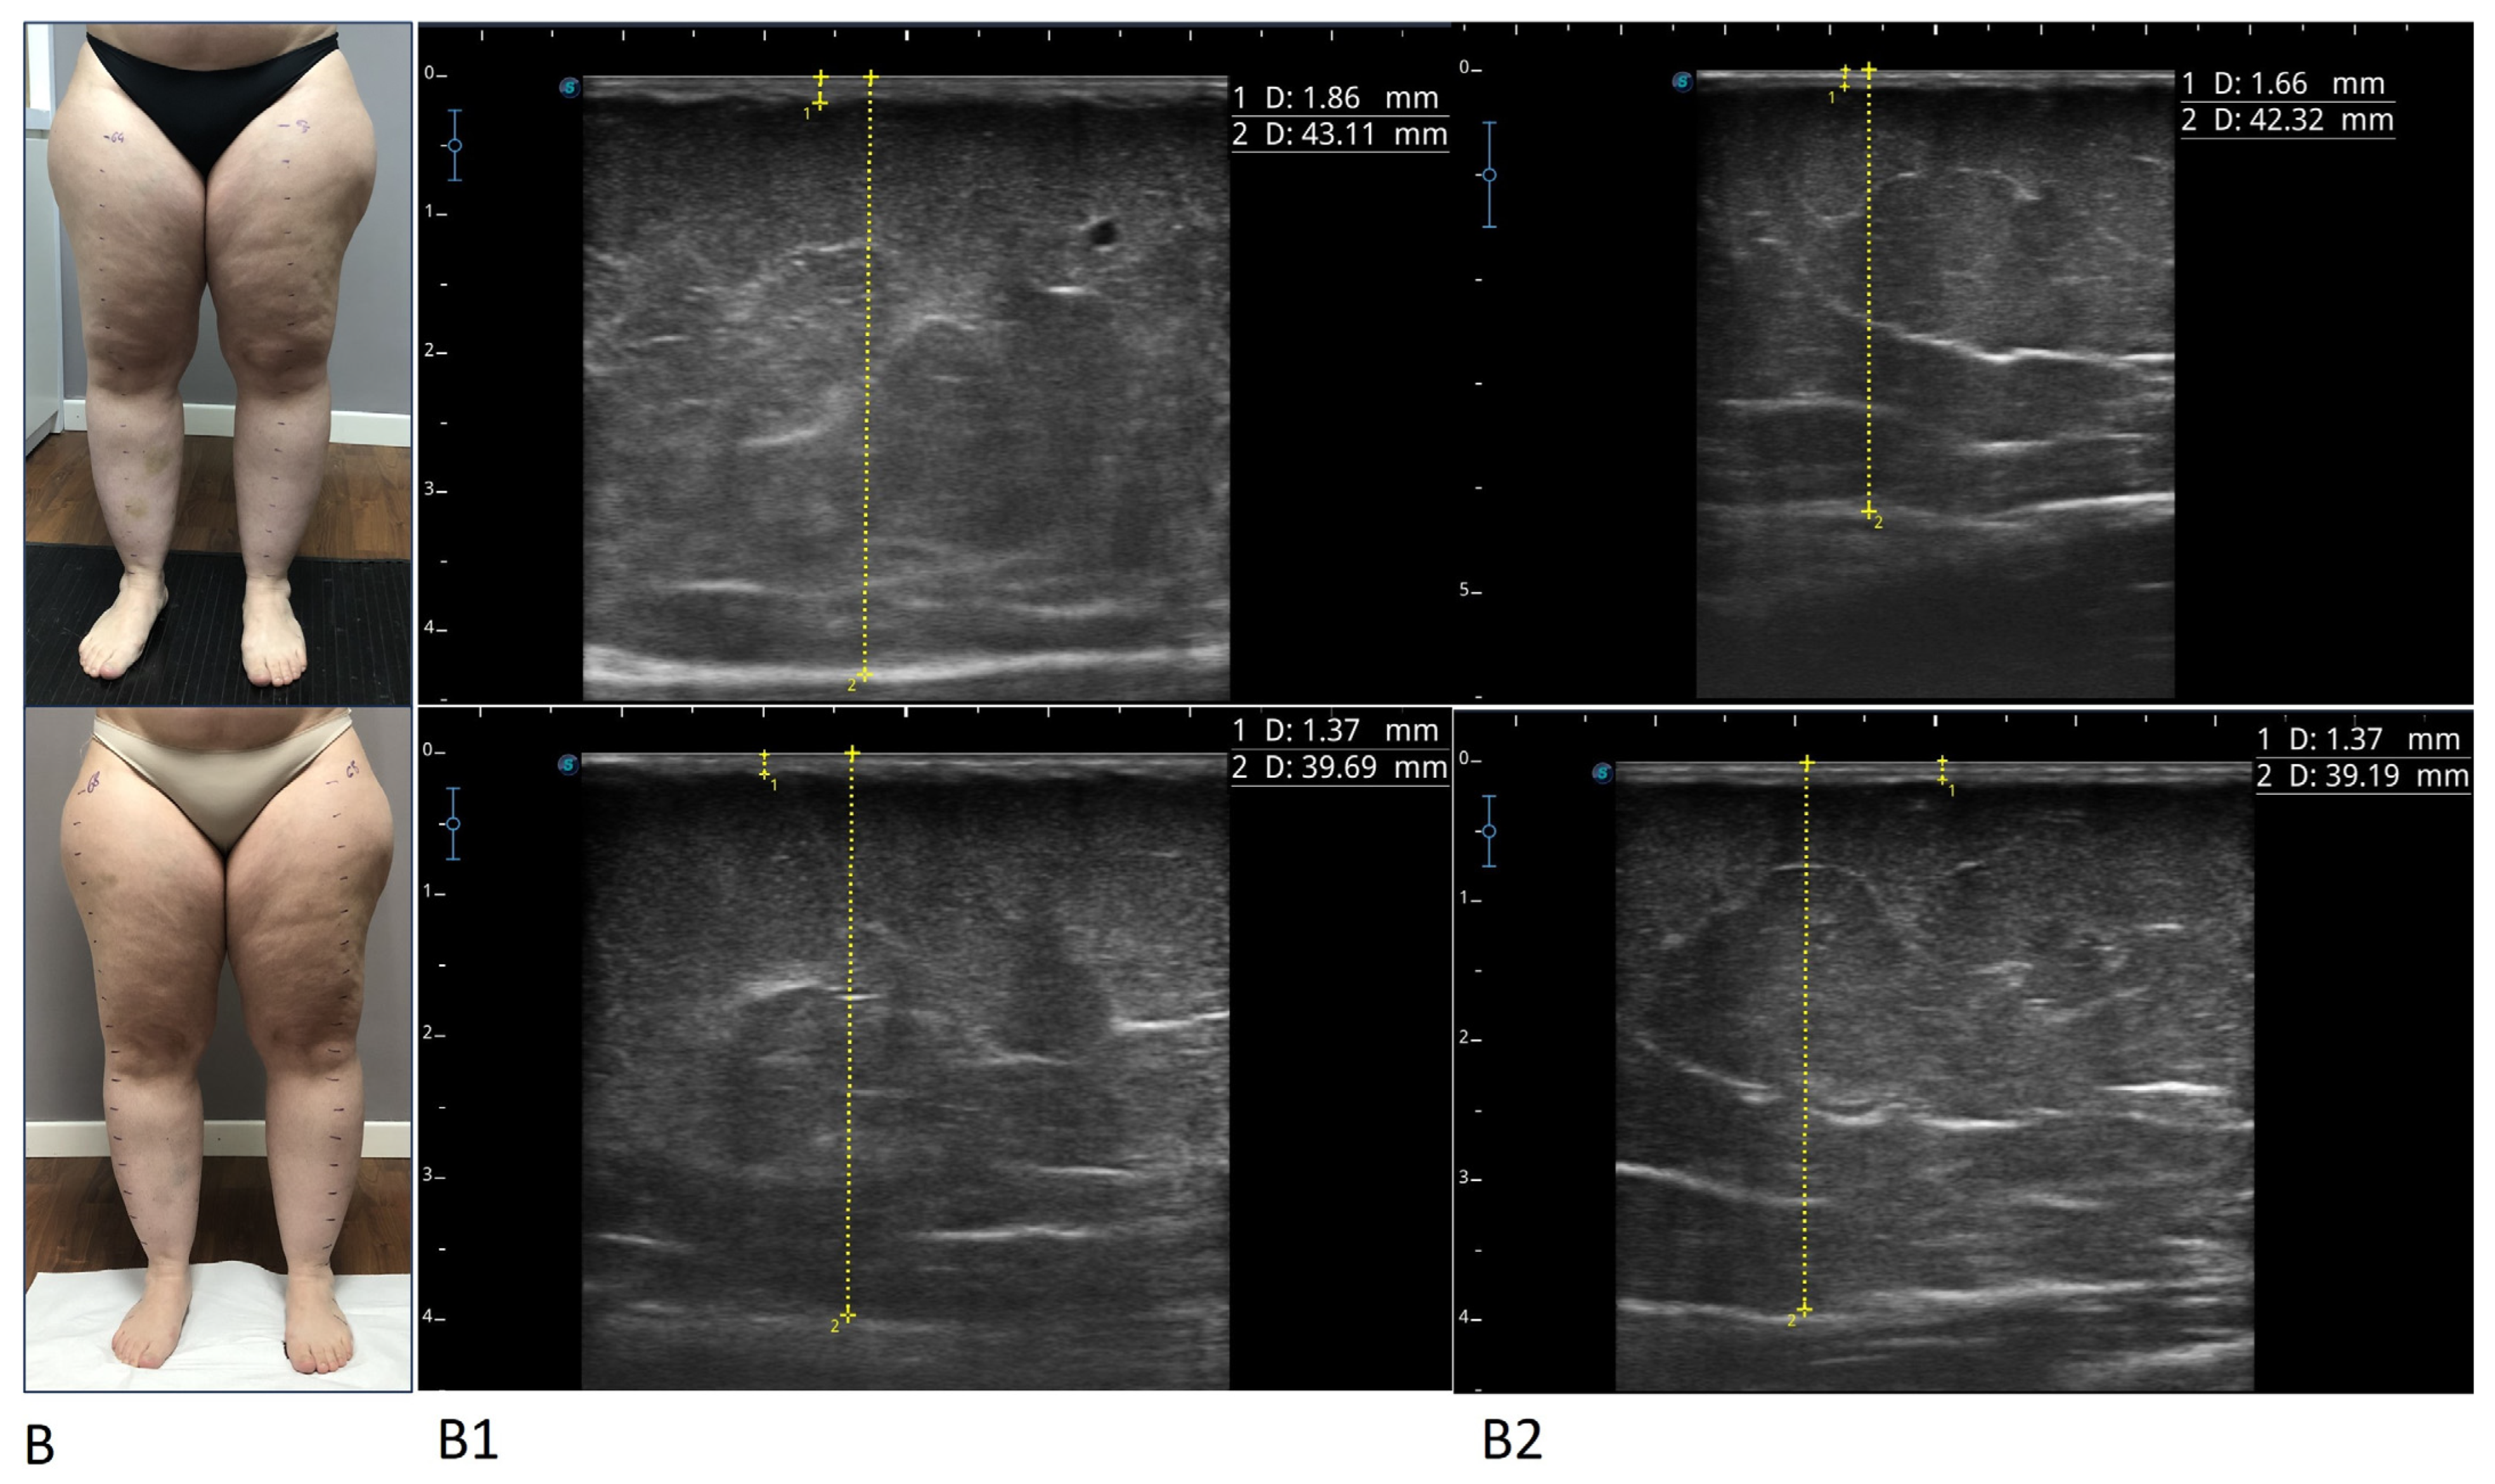

Figure 2.

Photographs and ultrasounds of two patients (A,B), before treatment (images above) and after treatment (images below). The ultrasound measurements are represented by the dashed yellow lines: the thickness of the skin was measured from the skin surface to the lower edge of the epidermis and dermis complex, and the thickness of the suprafascial superficial adipose tissue was measured from the skin surface to the subcutaneous transition structure (fascia). All imaging was performed using a high-frequency linear probe (8–14 MHz), keeping the probe perpendicular to the skin and always without applying pressure. For patient A, ultrasound images relating to the lower medial third of the leg (A1) and the upper lateral third of the leg (A2) before and after the treatment are shown (box above and box below, respectively). For patient B, ultrasound images relating to the lower medial third of the thigh (B1) and the upper medial third of the thigh (B2) before and after the treatment are shown (box above and box below, respectively).